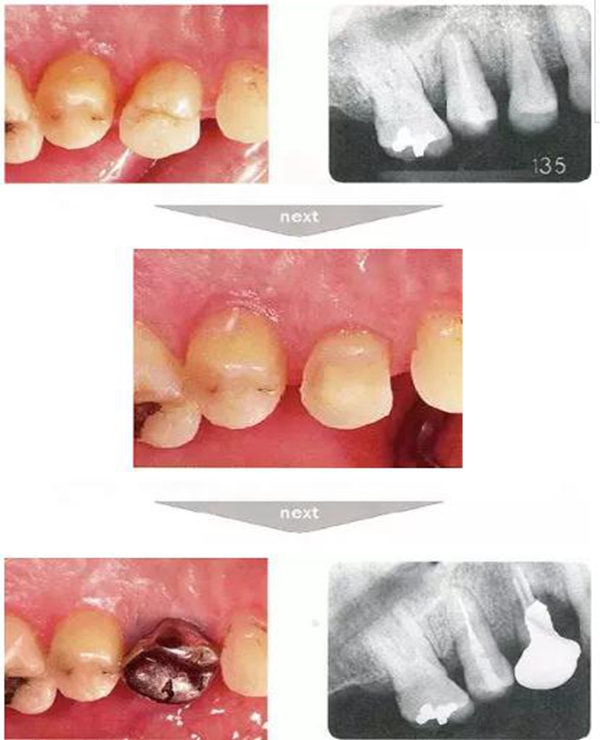

●與外傷相關的附著喪失①

右下4牙冠牙根破折案例。照片是破折前4個月拍攝的。牙周袋深度為3mm以下,牙周組織為正常狀態(tài)(右下5是以前由智齒矮小齒移植而來)。破折后,舌側咬頭破折至傾斜的牙根處,破折片與牙齦相連。

去除破折片進行了修復治療。3年后,上頜腭側有6mm、近中有4mm的牙周袋。X片可觀察到嚴重的骨吸收現(xiàn)象。可推斷出是破折引起的附著喪失。